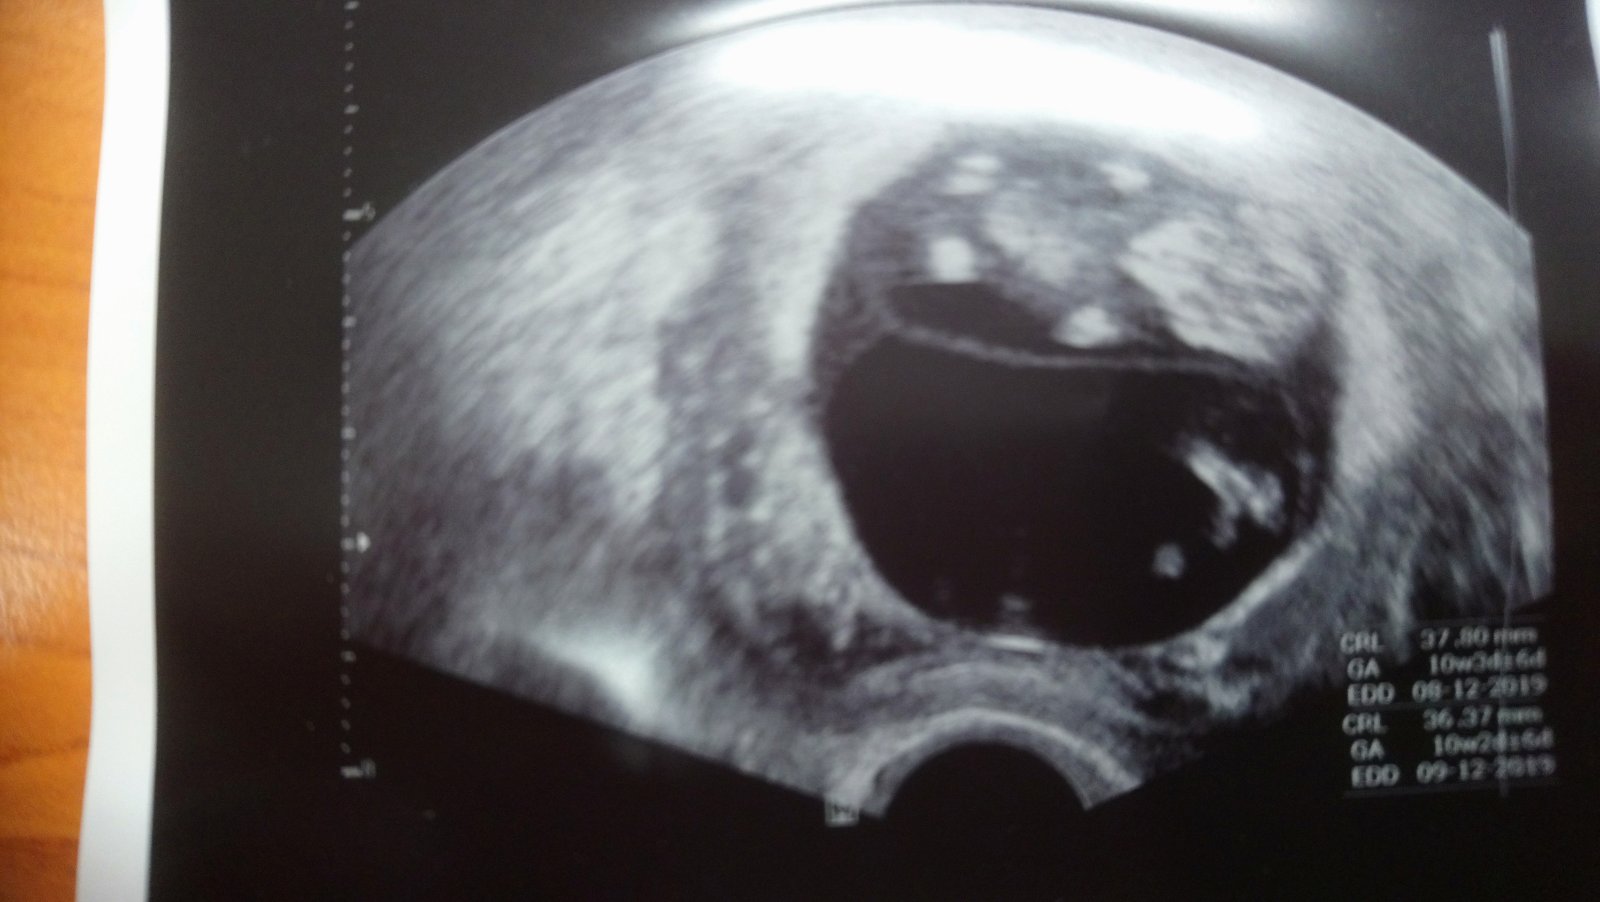

Ahoj holky! Tak druhá kontrola je úspěšně za námi má dvě ruce dvě nohy tak snad to bude dobrý 😀 Bylo super se dívat na té obrazovce jak se tam furt vrtí, málem jsem se tam rozbrečela 😅 Momentálně jsem 10+4 a genetika mě čeká za tři týdny, všem ostatním co je čeká kontrola přeji ať je vše O.K